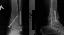

3 мая после ДТП у меня сложный перелом дистального метаэпифиза левой б/б кости, внутренней лодыжки, оскольчатый перелом наружной лодыжки с подвывихом стопы.

7.05.08 проведена операция: открытая репозиция, М.О.С. внутренней и наружной лодыжек слева. ТАФ сустава.

При обращении на консультацию врачи рекомендуют операцию артродез голеностопного сустава, как единственно возможный вариант. Р/снимки и выписка прилагаются.

Основная часть смещенных фрагментов суставной площадки большеберцовой кости не вправлена и не была фиксирована. Все уже срослось в неправильном положении. Восстановить форму суставной поверхности и трудно, и, главное, это не обеспечит здоровый сустав. Вариант с артродезом тут вполне уместен. Способность нормально ходить как раз артродез и обеспечит.